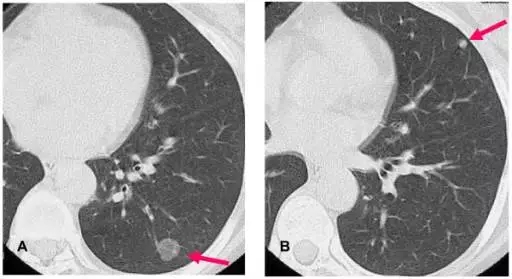

片来自Internet

一次肺部CT扫描产生200-300张片子,一个放射科医生全神贯注检查30个人的CT片子,需要150-180分钟。一家三甲医院平均每天接待200例左右的肺结节筛查患者,放射科医生每天至少需要读片4万张。这可以说是一种“劳役”般的工作,稍有疏忽,就会影响到诊断的准确率。